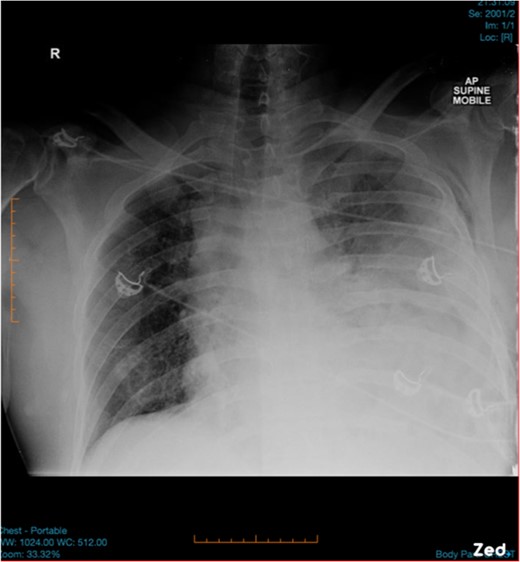

A 47-year-old male was brought to the Emergency department by ambulance after a high speed motor vehicle accident. On arrival, he had a Glasgow Coma Scale of 13, a patent airway with cervical spine collar in situ, spontaneous tachypnoeic breathing with an oxygen saturation of 97% on 15 l of oxygen. He had unequal breath sounds with decreased air entry on the left. He was tachycardic with a blood pressure of 110/70 mmHg. There were multiple bruises and abrasions to his torso and bilateral lower limbs. He had no previous medical history and was otherwise healthy. Initial chest x-ray was suspicious for a left-sided haemopneumothorax (Fig. 1) and an intercostal chest tube (ICCT) was inserted to the left side with a repeat x-ray confirming its position. However, there was minimal drain output and little swing. Subsequent computed tomography (CT) scan of the chest detected a left diaphragm rupture with a large diaphragmatic hernia where most of the left thorax was replaced by intra-abdominal contents (Fig. 2). A decision was made for emergency laparotomy to repair the diaphragmatic hernia. The patient was intubated in the emergency department prior to transfer to the operating theatre. While no ventilation problems were noted during transfer, the patient’s abdomen was seen to become progressively more distended to a point where it became tight and tympanic on percussion (Fig. 3). An underlying lung injury was suspected and the cardiothoracic team was called. At laparotomy, a significant pneumoperitoneum was confirmed with sudden escape of air upon entering the peritoneal cavity. The large hernia containing spleen, stomach and small bowel was reduced and the posterolateral diaphragmatic defect was repaired with a non-absorbable suture. This was followed by a left thoracotomy that identified a superficial laceration in the left upper lobe of the lung which was repaired with Prolene sutures and re-enforced with tissue glue. The patient was then transferred to the intensive care unit in a stable condition and made a good recovery. It is likely that the lung injury was caused secondary to intercostal catheter insertion during resuscitation in the Emergency Department. However, it could also have been secondary to associated left rib fractures or blunt trauma during the accident.

Pre-operative picture showing tension pneumoperitoneum with a very distended abdomen.